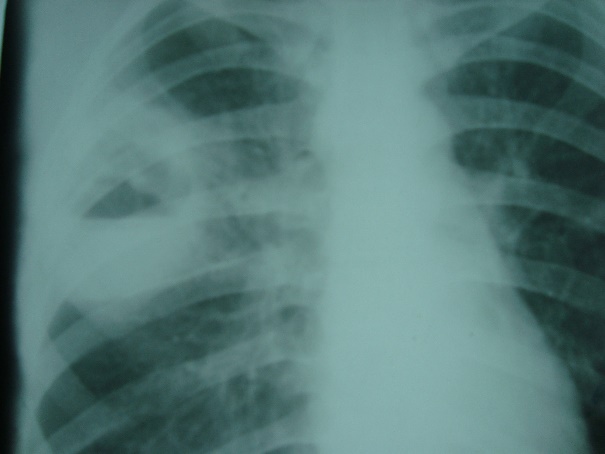

Какой патологический процесс в легких вы видите// Пневмония// Пневмоторакс// +гидропневмоторакс// Плеврит// рак легкого

Какой патологический процесс в легких вы видите// диссеминированный туберкулез легких// саркоидоз легких// +метастазы в легкие// альвеококкоз легких// эхинококкоз легких